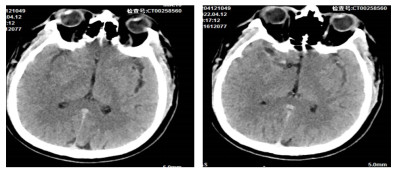

患者男性,51岁,于2022年4月12日19:50,因突发晕厥,伴左侧肢体无力、言语不清半小时就诊。查体:体温36.3 ℃,呼吸频率20次/min,脉率73次/min,血压118/99 mmHg(1 mmHg=0.133 kPa),SaO2 85%。神志清,精神差,双侧瞳孔等大等圆约3.5 mm,光反射灵敏,口角歪斜,言语不清,左上肢肌力3级,左下肢肌力2级。既往无高血压病史。急诊床旁检验检查示:D-二聚体5.158 µg/mL、肌红蛋白107.86 ng/mL;动脉血气示:PaO2 33.9 mmHg、FO2Hb 64.6%、FHHb 30.1%、k+ 3.3 mmol/L、血乳酸(lactic acid, Lac)3.3 mmol/L,心电图排除ST抬高型心梗,头颅CT示(见图 1):右侧大脑中动脉密度增高,建议MRI及CTA进一步检查。请卒中医生会诊考虑:急性脑梗死和肺栓塞。随后患者出现恶心、呕吐、吐物为胃内容物,20:00血压突降至57/43 mmHg,烦躁不安、口唇、面色苍白、肢体末梢冰冷,给予复方氯化钠注射液500 mL、生理盐水500 mL扩容、生理盐水200 mL+多巴胺注射液200 mg升压治疗,20:14血压95/60 mmHg、SaO2 95%(鼻导管4 L/min)。20:34血压86/53 mmHg,烦躁,呼吸困难,左侧肢体肌力为0级,给予气管插管氧疗。20:50血压100/62 mmHg、SaO2 95%,左侧上、下肢肌力0级,右侧肌力5级,左侧浅感觉较右侧差,深感觉正常,双侧跟、膝腱反射存在,左侧巴彬斯基征(+),余(-)。初步考虑:急性脑梗死和急性肺栓塞。

图 1 患者CT头颅平扫